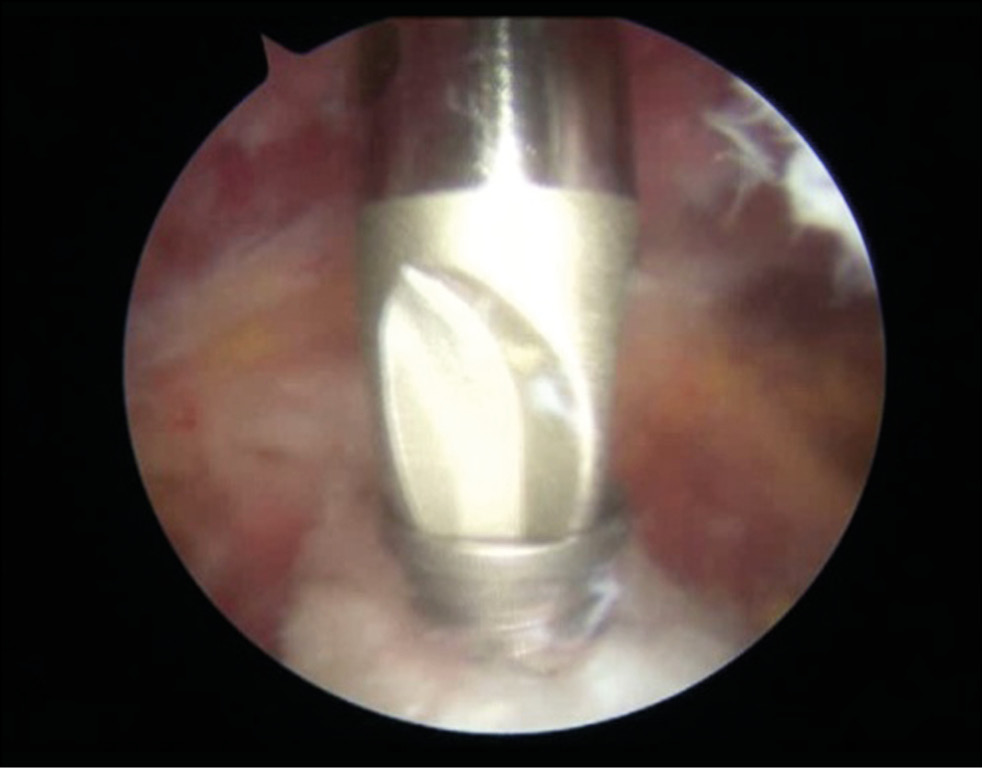

Using the installed guide pins, channels for the sleeves were formed with a three-level drill, thereby reducing the probability of splitting the coracoid process during osteotomy (Fig. 10). Two cannulated sleeves were placed into these channels using a guide (Fig. 11).

Fig. 10. Preparation of channels for guide sleeves in the coracoid process: a — formation of channel No. 1 using a guide pin; b — drilling channel No. 2 for the guide sleeve.

Fig. 11. Installation of sleeves in the coracoid process.